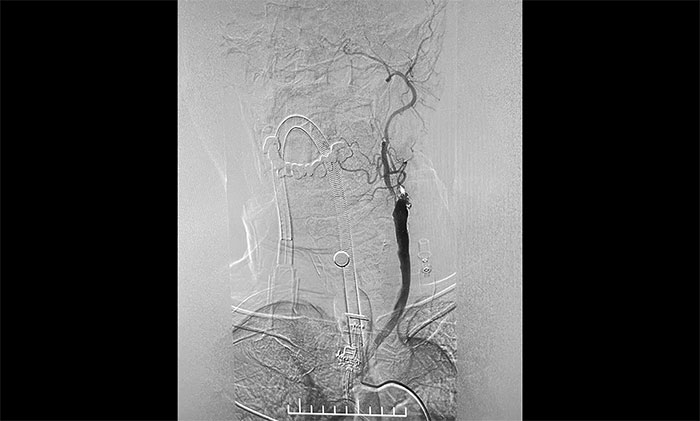

腦血管造影顯示,左頸總動(dòng)脈起始段、下段中度狹窄,左頸外動(dòng)脈起始段重度狹窄,左頸內(nèi)動(dòng)脈起始段閉塞,遠(yuǎn)端頸內(nèi)動(dòng)脈緩慢顯影至眼動(dòng)脈;左椎動(dòng)脈、左大腦后動(dòng)脈、基底動(dòng)脈顯影,左椎V4段經(jīng)側(cè)枝向左側(cè)枕動(dòng)脈代償供血至左頸外動(dòng)脈;右頸內(nèi)動(dòng)脈起始段輕度狹窄。

術(shù)中,超滑導(dǎo)絲、多功能導(dǎo)管經(jīng)過反復(fù)嘗試順利通過左頸內(nèi)動(dòng)脈起始段,到達(dá)左頸內(nèi)動(dòng)脈遠(yuǎn)端顯影段,路圖見遠(yuǎn)端血管通暢,左大腦中動(dòng)脈顯影;隨后,微導(dǎo)絲經(jīng)多功能導(dǎo)管置于左頸內(nèi)動(dòng)脈海綿竇段,經(jīng)微導(dǎo)絲送入保護(hù)傘至左頸內(nèi)動(dòng)脈巖骨垂直段并釋放,再沿保護(hù)傘微導(dǎo)絲送入4x30mm球囊于左頸內(nèi)動(dòng)脈起始段,給予球囊擴(kuò)張,撤除球囊后造影見左頸內(nèi)動(dòng)脈起始段再通,左頸內(nèi)動(dòng)脈、左大腦中動(dòng)脈顯影;最后,送入9x50mm支架,釋放于左頸內(nèi)動(dòng)脈頸段至左頸總動(dòng)脈末段,造影見左頸內(nèi)動(dòng)脈起始段顯影明顯改善,左頸內(nèi)動(dòng)脈、左大腦中動(dòng)脈、左大腦前動(dòng)脈顯影可,行3D造影見左頸內(nèi)動(dòng)脈頸段顯影改善。行支架CT見支架成形可,行XperCT未見顱內(nèi)出血。

▲ DSA確診左側(cè)頸內(nèi)動(dòng)脈閉塞